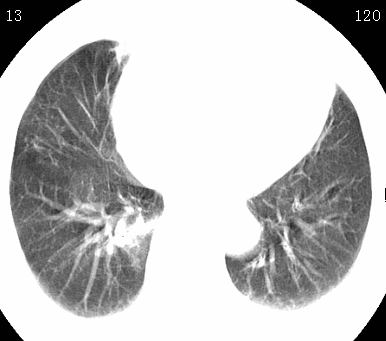

标题: CT26680:肺部右下肺静脉干结节的界定 [打印本页]

标题: CT26680:肺部右下肺静脉干结节的界定

经追查说有支扩咯血病史,但不确定

考虑1、周围型肺癌,2肺静脉畸形,前者可能大,建议增强检查。

考虑1、周围型肺癌,2肺静脉畸形,前者可能大,建议增强检查。支持!

不排除右肺下叶周围型肺癌可能。

中心型肺癌,纤支镜可帮助明确。